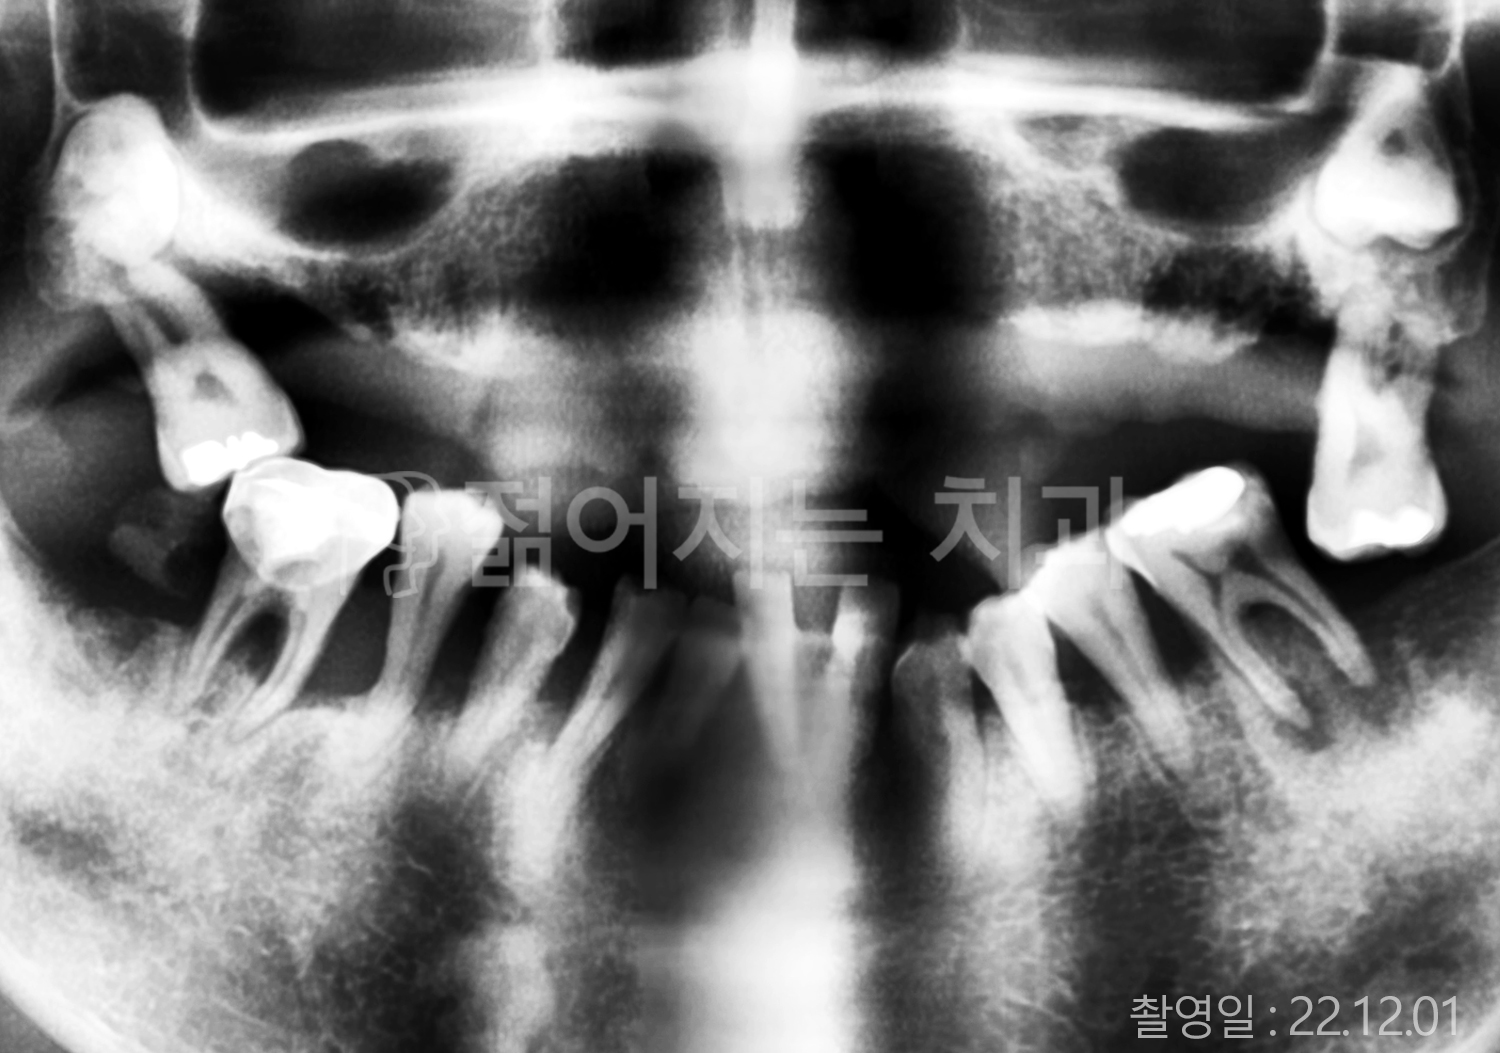

• 50대 고혈압, 당뇨, 고지혈증 전체치아 10개 이상 임플란트

• 60대 골다골증, 간경화 전체치아 10개 이상 임플란트

• 60대 고혈압, 고지혈증 전체치아 10개 이상 임플란트

• 50대 고혈압, 당뇨 전체치아 10개 이상 임플란트